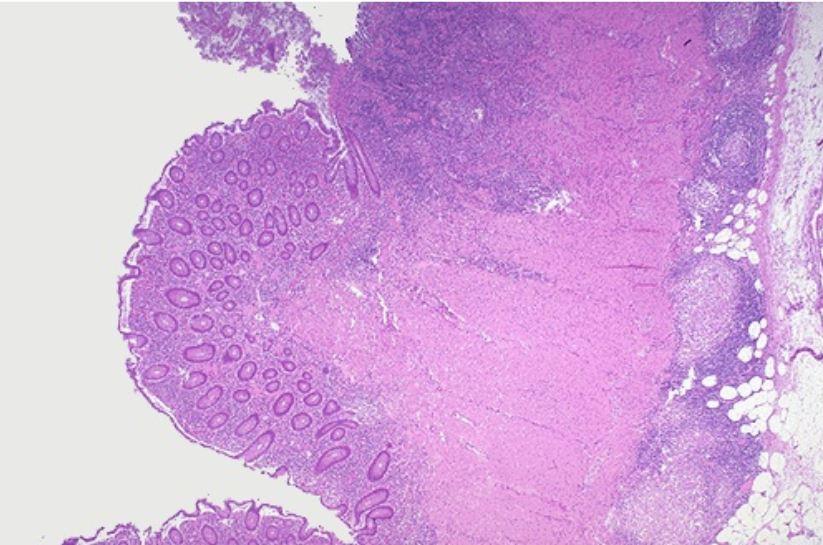

125

card image

crohns histo

126

Which histologic feature is most characteristic of Crohn disease?

A. Caseating granulomas

B. Non-caseating granulomas

C. Reed–Sternberg cells

D. Psammoma bodies

Which additional microscopic finding is commonly seen in Crohn disease?

A. Crypt abscesses

B. Fat necrosis

C. Fibrous plaques

D. Amyloid deposits